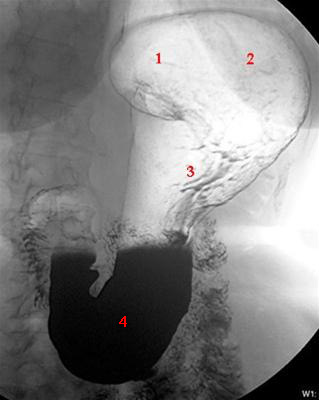

Mavesækken (ventrikel) vist på en røntgenundersøgelse med dobbelt kontrast-teknik (kontraststof er barium) og luft hos en stående patient. Denne undersøgelse foretages ret sjældent idag, hvor der oftest anvendes CT-skanning.

1. Cardia (mavemund)

2. Fundus (mavesæk øvre del)

3. Corpus (mavesæk midterste)

4. Antrum (mavesæk nederste del)